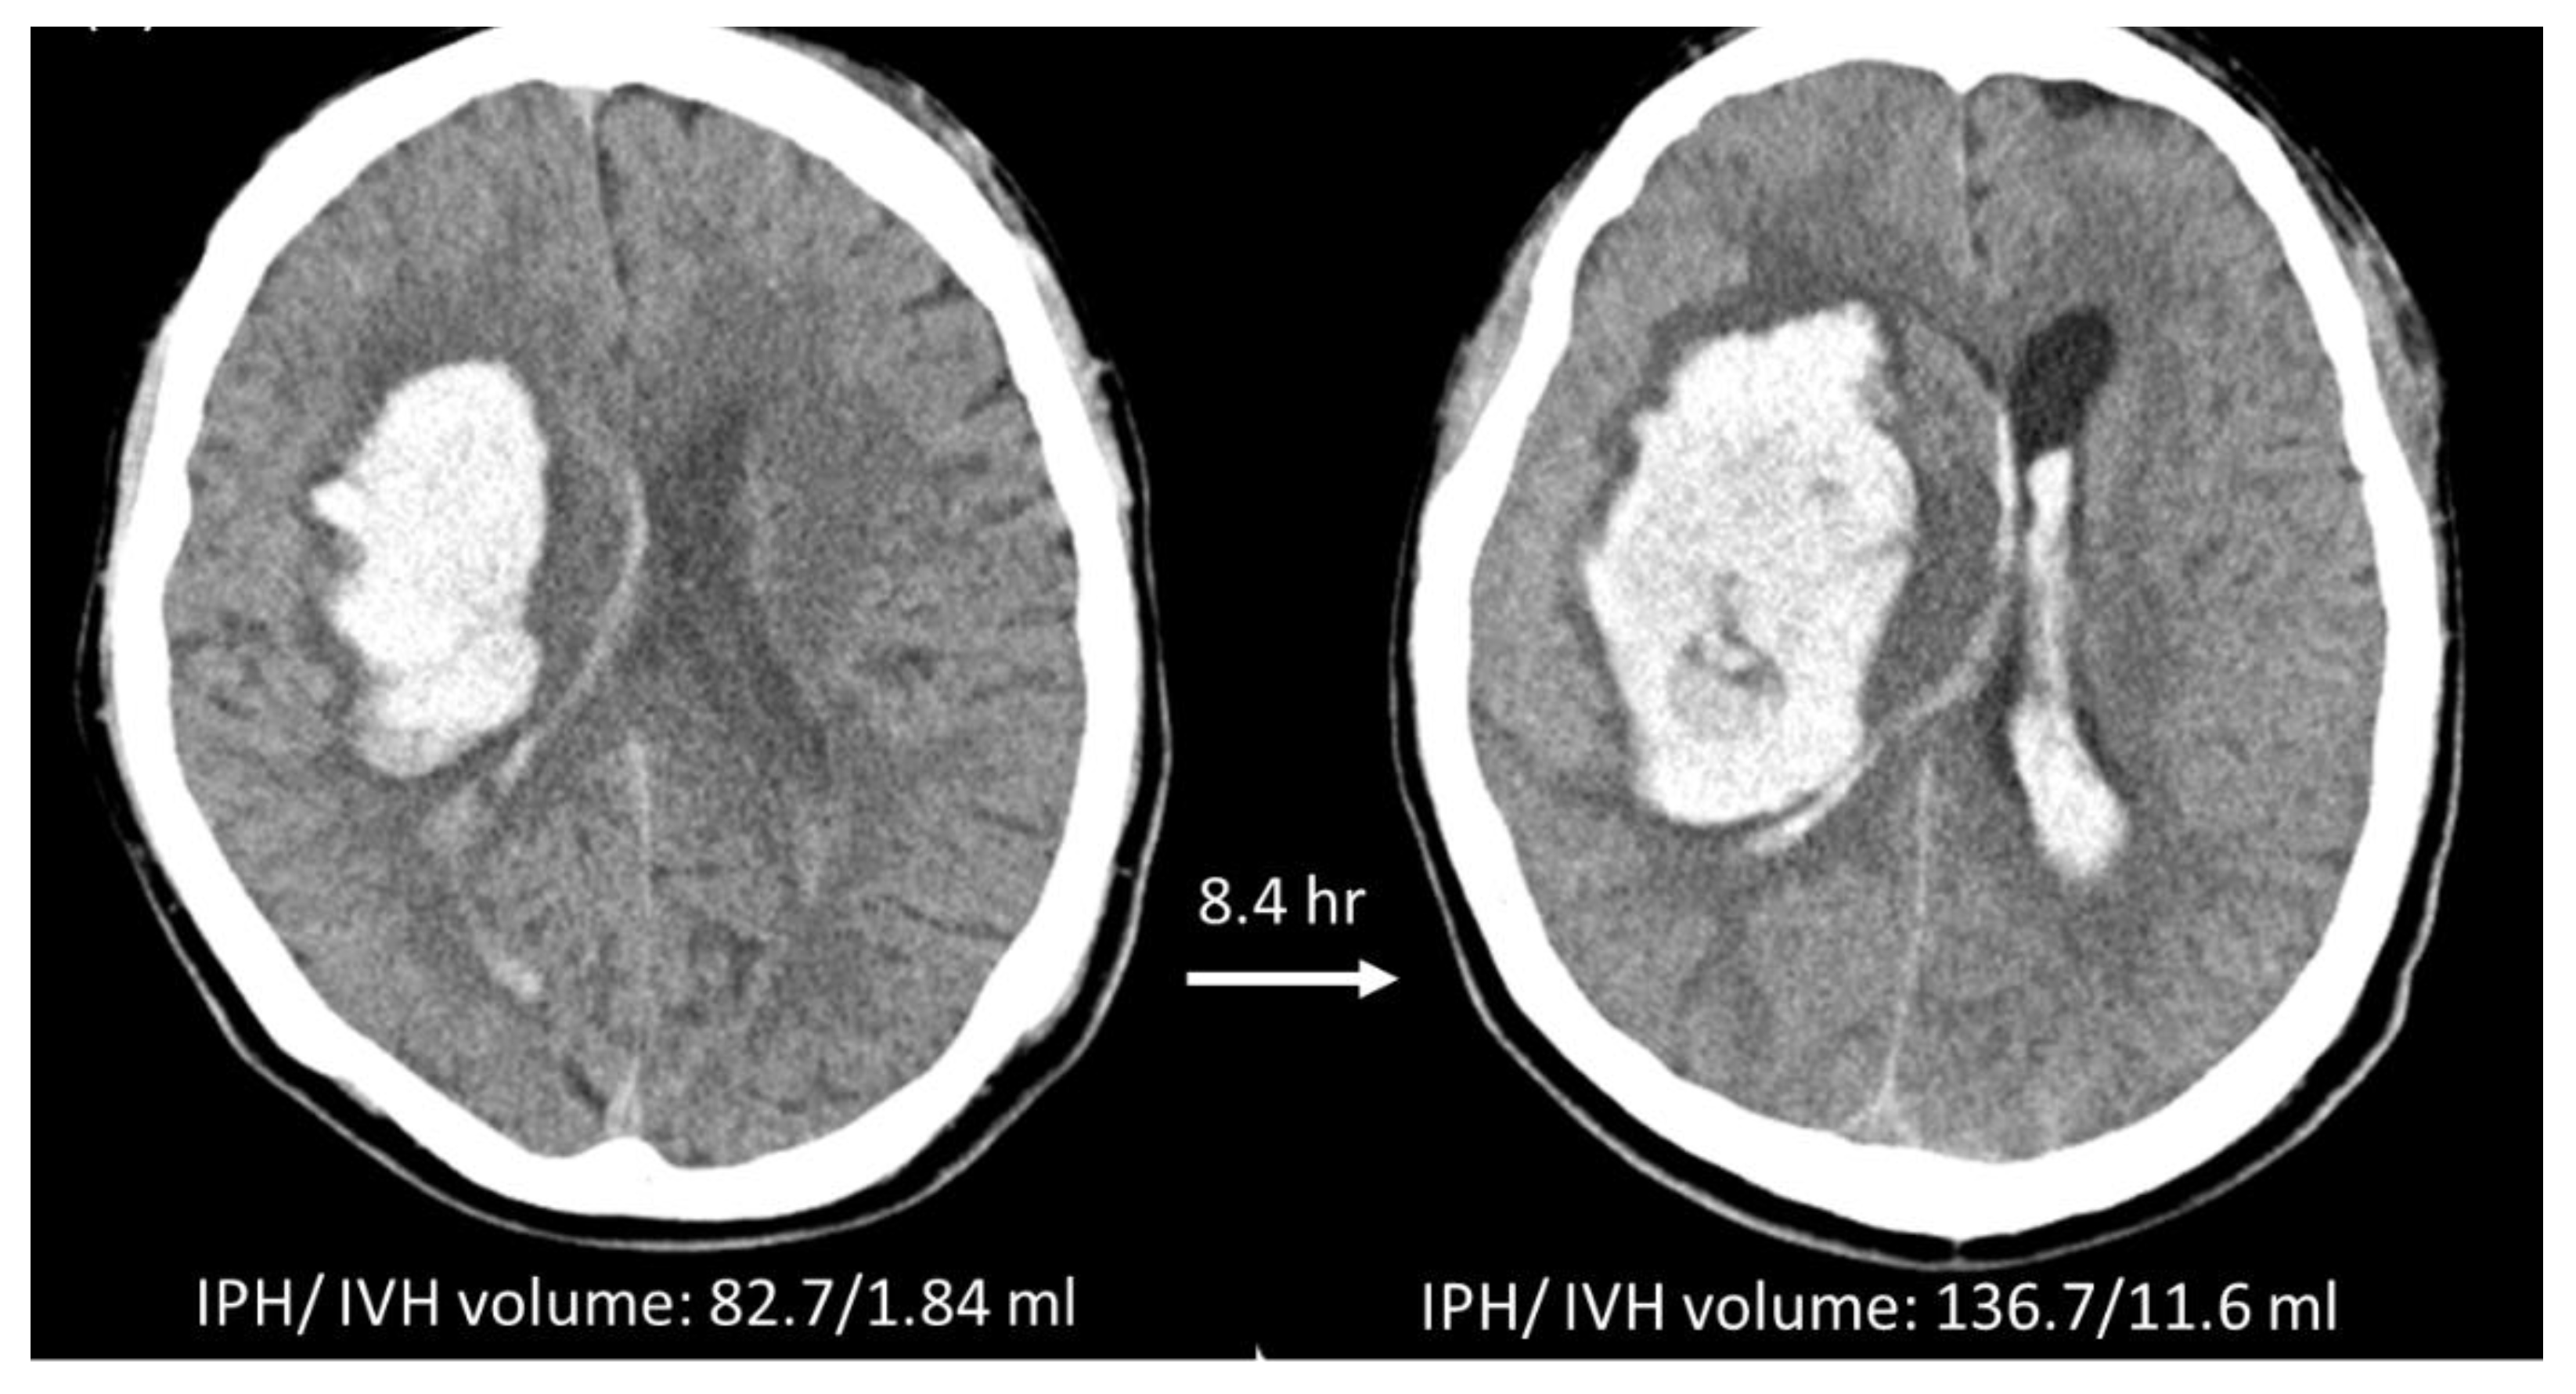

2.5. Manual Hematoma Segmentation and HE Definition

3.2. Hematoma Expansion Status Defined by IPH + IVH (HEP+V)

3.3. HE Prediction Performance of Two Radiomics Models